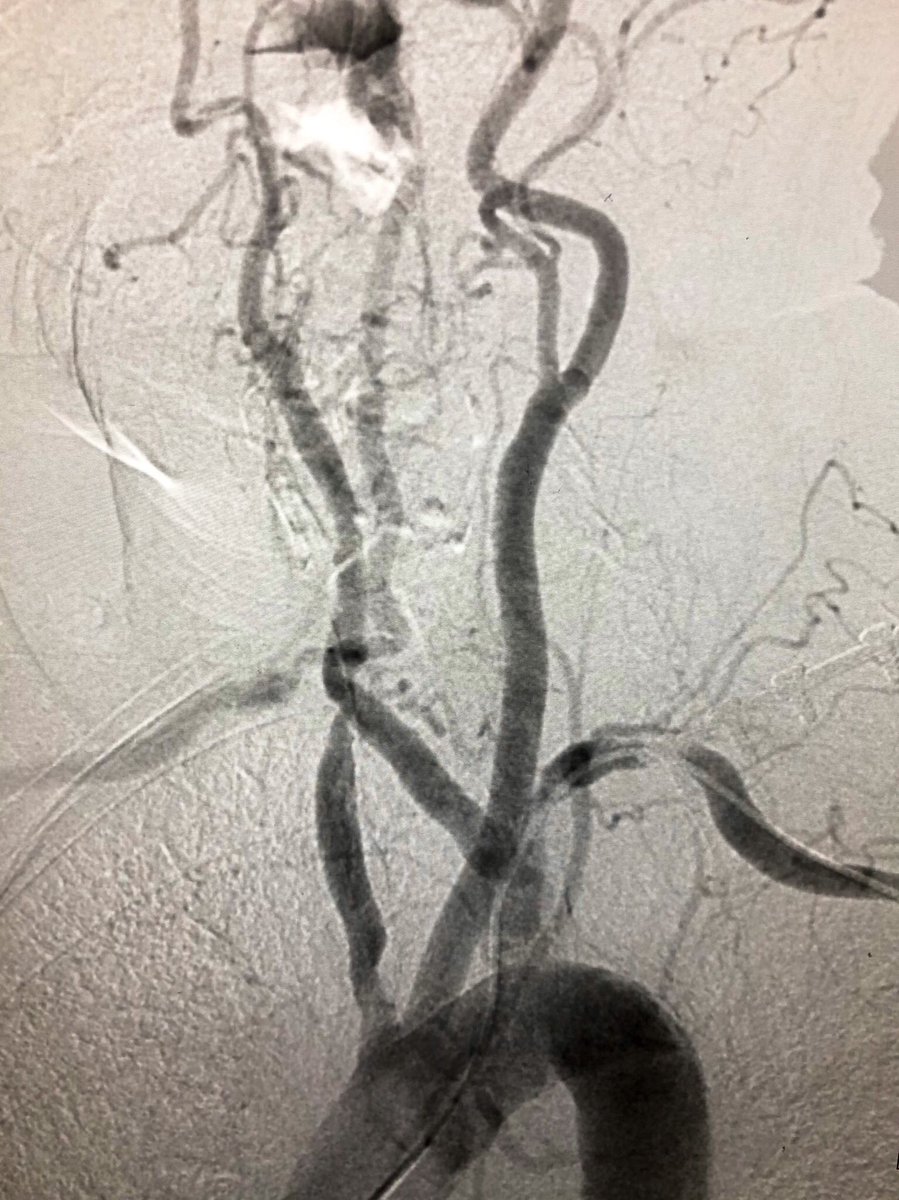

Hard to fully appreciate on still image. Selective angiography images included -R CCA stenosis and R ICA occlusion -aberrant R SCA (Arteria Lusoria) occluded after the R vertebral origin - moderate L SCA disease with L vertebral occlusion #SCAIPAD #ACCFIT #RadialFirst

-R CCA stenosis and R ICA occlusion

-aberrant R SCA (Arteria Lusoria) occluded after the R vertebral origin

- moderate L SCA disease with L vertebral occlusion